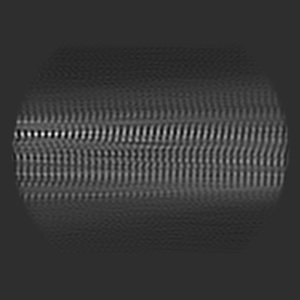

Structure of TDP-43 amyloid filaments from type A FTLD-TDP (individual 3, variant 1)

Sample: TDP-43 amyloid filaments extracted from the frontal cortex of an individual with type A FTLD-TDP

TDP-43 forms amyloid filaments with a distinct fold in type A FTLD-TDP.

Arseni D , Chen R, Murzin AG, Peak-Chew SY , Garringer HJ , Newell KL, Kametani F , Robinson AC , Vidal R , Ghetti B , Hasegawa M , Ryskeldi-Falcon B

(2023) Nature , 620 , 898 - 903